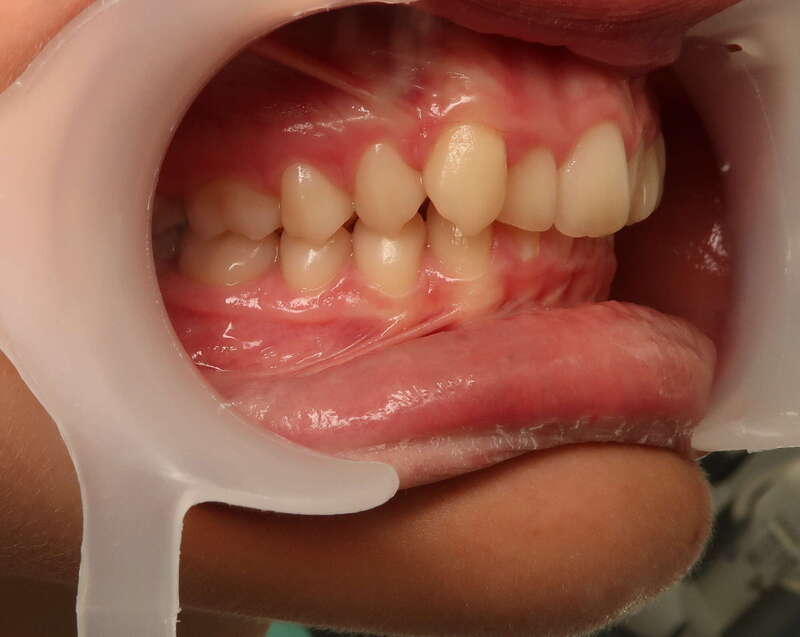

Ce cas d’interception chez un enfant de 8 ans démontre l'efficacité des aligneurs pour corriger des troubles fonctionnels précoces. Le diagnostic présentait des inversions d'articulé provoquant une déviation de la mandibule vers la gauche et un décalage des milieux.

Grâce à une coopération exemplaire et un traitement totalement indolore, l'expansion de l'arcade a permis de recentrer la mâchoire. Cette intervention a littéralement remis la croissance sur les rails, neutralisant le risque d'asymétrie faciale squelettique.

• Correction fonctionnelle : Recentrage immédiat de la mandibule et des milieux inter-incisifs.

• Prévention : Création d'un environnement favorable pour les dents définitives à venir.

• Bien-être : Approche douce respectant le confort de l'enfant.

C'est une étape fondamentale qui simplifie l'avenir orthodontique du patient tout en garantissant un développement facial harmonieux.

Avant